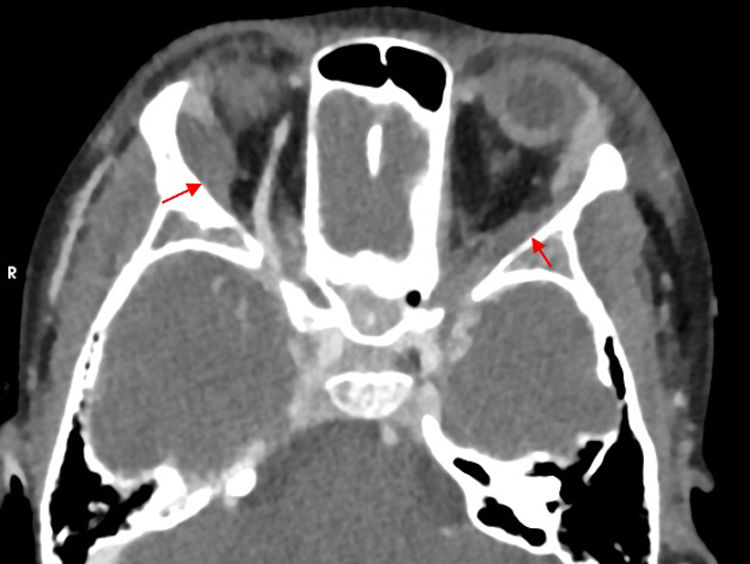

We present the case of an eight-year-old patient with sickle cell disease homozygous for HbS (with no family history) managed with prophylactic amoxicillin, hydroxyurea and folic acid, under annual follow-up, with a previous admission due to a vaso-occlusive crisis in the leg and no other relevant history. She was admitted to the sending hospital with suspected vaso-occlusive crisis in the extremities and abdominal pain and transferred to our hospital due to progressive deterioration with fever, hepatomegaly and splenomegaly extending to the iliac crest, in addition to painful bilateral periocular edema in absence of phlogosis or changes in vision (Fig. 1). The bloodwork revealed a decreased hemoglobin concentration and platelet count and elevated hemolysis markers, with a proportion of sickle hemoglobin (HbS) of 44.3% and a C-reactive protein level of 17.7 mg/dL. Splenic sequestration and orbital cellulitis were suspected,1,2 leading to administration of supplemental oxygen, analgesia with continuous infusion of morphine, two red blood cell transfusions and intravenous antibiotherapy. The orbital CT scan (Fig. 2) showed bilateral involvement of soft tissues in the outer periorbital region, bordering the orbital rim and extending posteriorly, a finding that could be compatible with extramedullary hematopoiesis or a lymphoproliferative disorder. The head MRI (Fig. 3) ruled out nervous system involvement and showed areas suggestive of infarction in the great wings of the sphenoidal bones with secondary hemorrhagic effusion.3 The blood culture and the antibody test for Epstein-Barr virus were negative. A diagnosis of bone infarction was made and antibiotherapy discontinued, with full clinical resolution in seven days.